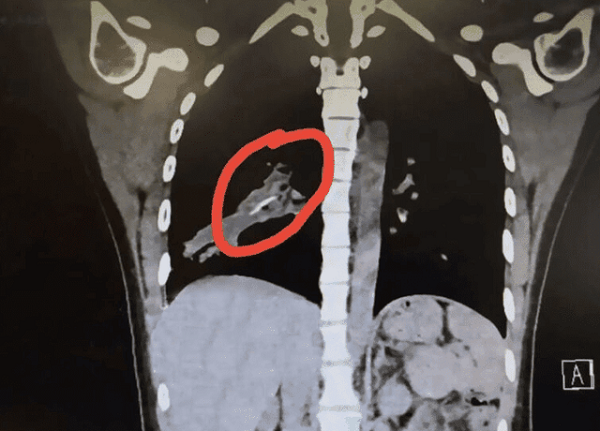

Hình ảnh chụp CT của bệnh nhân cho thấy có một vật thể lạ trong phổi. |

Các bác sĩ ở bệnh viện Đại học Y Quảng Châu đã yêu cầu bệnh nhân chụp CT. Kết quả cho thấy có một vật thể lạ nằm trong phổi. Vào ngày 12/4, bác sĩ Dương Minh đã thực hiện nội soi và sau 30 phút kiên trì, đã gắp thành công 1 miếng xương nhỏ dài khoảng 2cm. Bác sĩ Minh cho rằng đây là xương gà hoặc vịt.

Miếng xương không biết bằng cách nào đã chui tọt vào phổi, sau khi được gắp ra, tình trạng khó thở và ho suốt 14 năm qua của bệnh nhân lập tức chấm dứt.